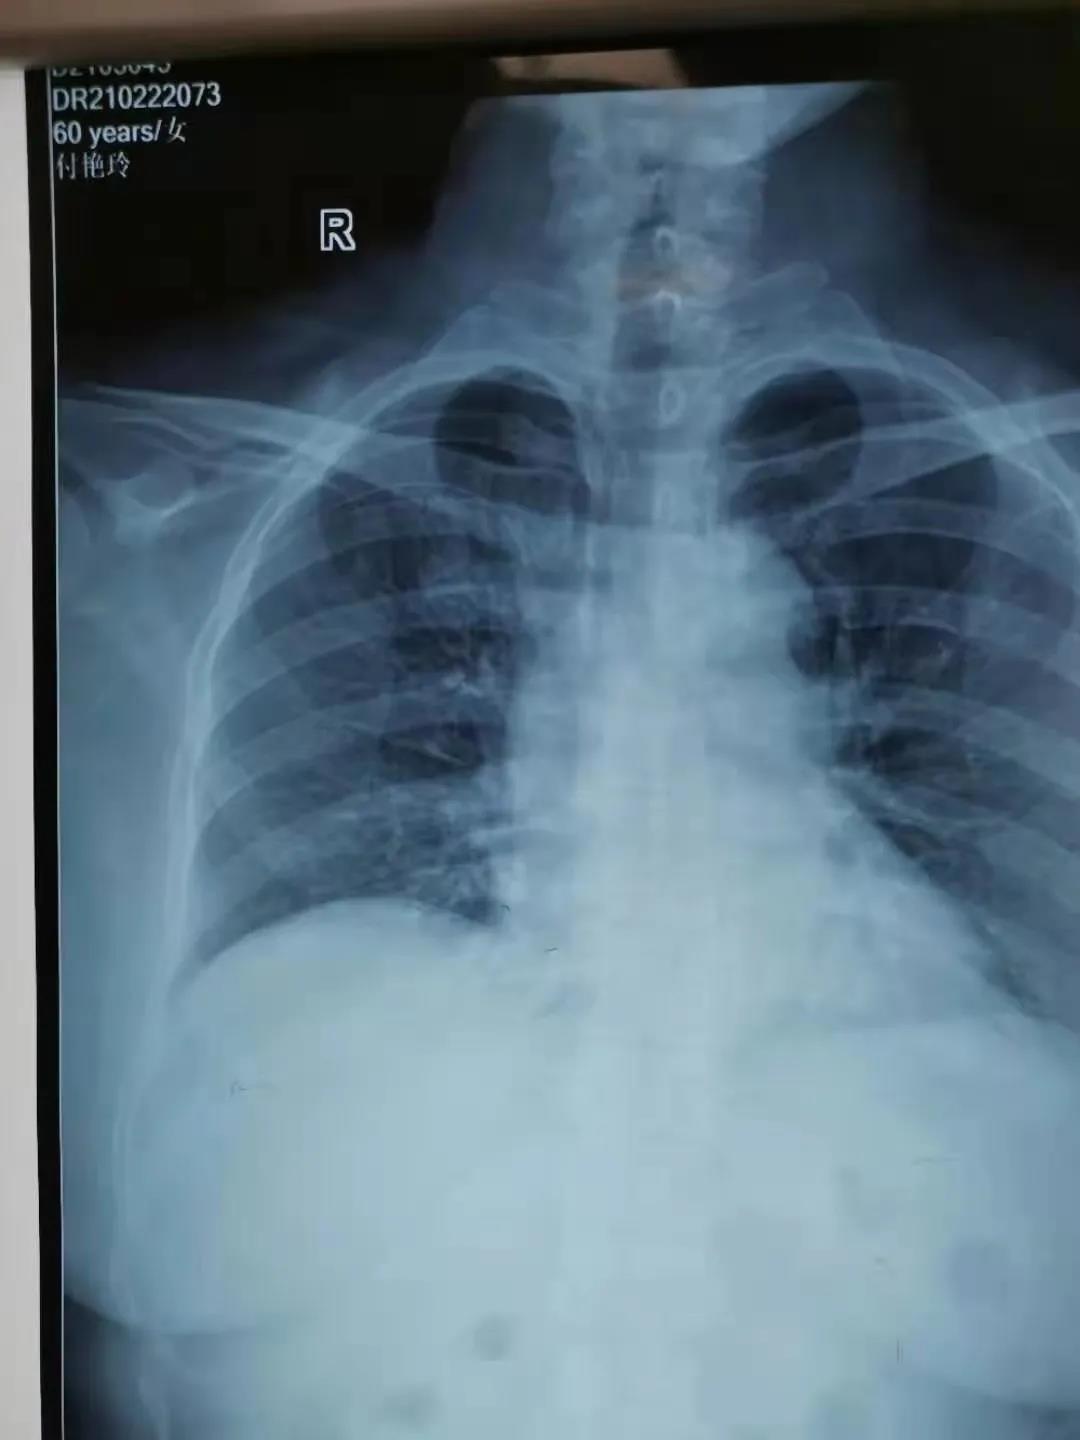

2月22日,由鄲城縣第二醫(yī)療健康服務(wù)集團(tuán)鄲城縣中醫(yī)院腫瘤血液科護(hù)士長(zhǎng)劉曉娟,護(hù)士丁星文、馬慧、張玉霞成立的靜脈治療專科小組,在經(jīng)過了數(shù)例PICC置管中進(jìn)行心電腔內(nèi)(ECG)定位與x線下定位結(jié)果的比較后成功運(yùn)用了ECG定位技術(shù)置管,此項(xiàng)技術(shù)的成功開展,標(biāo)志著醫(yī)院PICC置管定位技術(shù)又上新臺(tái)階!

ECG腔內(nèi)定位技術(shù)是一種在置管過程將特殊的心電導(dǎo)聯(lián)線聯(lián)接導(dǎo)管導(dǎo)絲和心電圖機(jī),在送入導(dǎo)管過程中通過觀察心電圖上P波的特征性變化來判斷導(dǎo)管尖端的位置的方法,此項(xiàng)技術(shù)實(shí)現(xiàn)了在術(shù)中實(shí)時(shí)定位和調(diào)整導(dǎo)管頭端,達(dá)到精準(zhǔn)定位PICC導(dǎo)管頭端位置的目的。

ECG定位技術(shù)通過一“進(jìn)”兩“退”的方式(一進(jìn):當(dāng)導(dǎo)管尖端到達(dá)CAJ時(shí),可見高尖P波,進(jìn)入右心房后P波雙向,由高尖再轉(zhuǎn)低;一退:當(dāng)導(dǎo)管尖端從右心房退回上腔靜脈時(shí)P波恢復(fù)正常。再退:導(dǎo)管繼續(xù)后退2-3 cm到達(dá)最終正確的位置。)判斷導(dǎo)管尖端位置,及時(shí)糾正導(dǎo)管異位、極大的提高了導(dǎo)管尖端位置定位的準(zhǔn)確性,避免了因反復(fù)調(diào)整導(dǎo)管位置所致的并發(fā)癥(靜脈炎、導(dǎo)管相關(guān)感染、血栓等)及因?qū)Ч墚愇欢貜?fù)拍片,保證了患者安全,提高了工作效率。③7